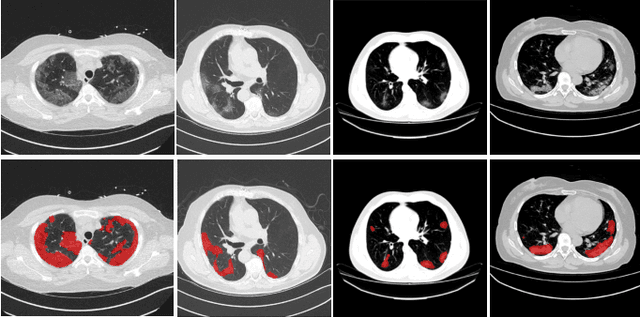

Abstract:The novel Coronavirus disease (COVID-19) is a highly contagious virus and has spread all over the world, posing an extremely serious threat to all countries. Automatic lung infection segmentation from computed tomography (CT) plays an important role in the quantitative analysis of COVID-19. However, the major challenge lies in the inadequacy of annotated COVID-19 datasets. Currently, there are several public non-COVID lung lesion segmentation datasets, providing the potential for generalizing useful information to the related COVID-19 segmentation task. In this paper, we propose a novel relation-driven collaborative learning model for annotation-efficient COVID-19 CT lung infection segmentation. The network consists of encoders with the same architecture and a shared decoder. The general encoder is adopted to capture general lung lesion features based on multiple non-COVID lesions, while the target encoder is adopted to focus on task-specific features of COVID-19 infections. Features extracted from the two parallel encoders are concatenated for the subsequent decoder part. To thoroughly exploit shared knowledge between COVID and non-COVID lesions, we develop a collaborative learning scheme to regularize the relation consistency between extracted features of given input. Other than existing consistency-based methods that simply enforce the consistency of individual predictions, our method enforces the consistency of feature relation among samples, encouraging the model to explore semantic information from both COVID-19 and non-COVID cases. Extensive experiments on one public COVID-19 dataset and two public non-COVID datasets show that our method achieves superior segmentation performance compared with existing methods in the absence of sufficient high-quality COVID-19 annotations.